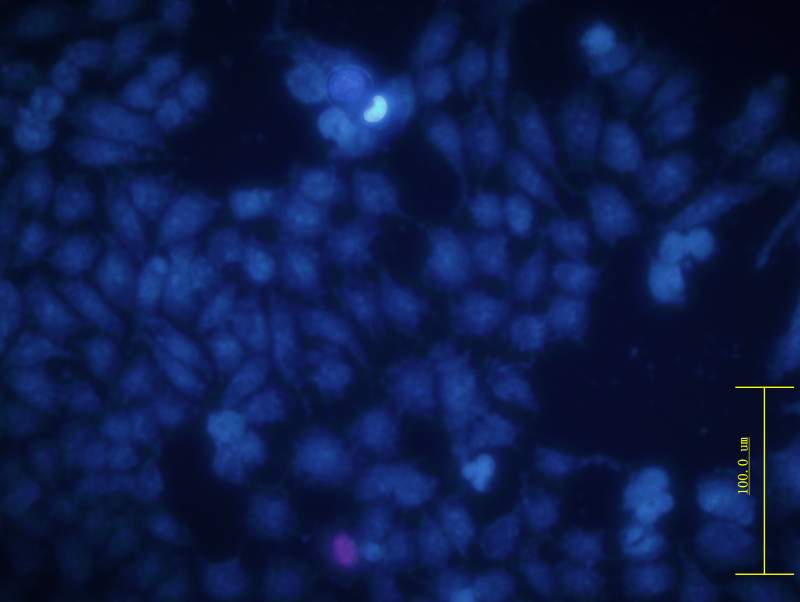

ϸ°û¾­¹ýÎïÀí½áºÏ»¯Ñ§ÁÆ·¨36 Сʱºó£¬ ÓÃhoechst Ⱦɫ ºÍPIȾɫ£¬¹Û²ìÆÚÐÎ̬¡£

37T4.jpg

¸ßÀ¶É«£ºµòÍöÂð£¿